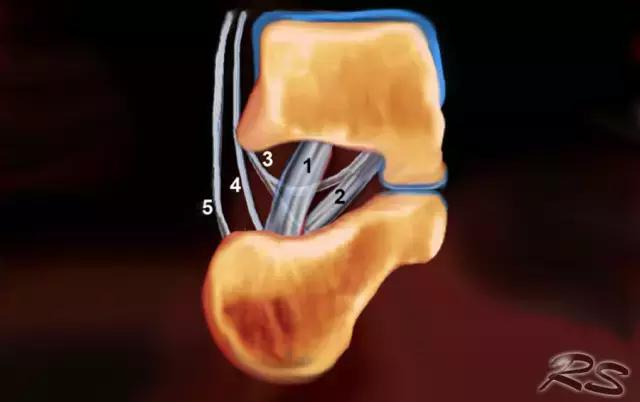

跗骨窦是锥形空腔,在后内侧到前外侧方向上延伸。它位于距骨的颈部和跟骨的前上表面之间的脚的外侧面。跗骨窦内侧继续作为跗管,这是距骨与跟骨间一个漏斗形的空间。它包含脂肪,动脉吻合,关节囊,神经末梢和五个韧带结构 - 下伸肌视网膜的内侧,中间和侧根; 颈韧带; 和骨间骨骨膜韧带(图)。

超声引导的跗骨窦的注射在右手侧与外侧入路。探头保持在冠状倾斜平面中。针沿着探头的长轴引入。

使用超声波可以容易地观察窦性骨壁。患者转向对侧,将待治疗的足以其内侧表面靠在桌面上,脚的外侧位于最上面。探头保持在关于脚的冠状平面中。

在跗骨窦被识别为跟骨的前处理和距骨颈之间的三角空间。针(箭头)的前端的锥形跗骨窦,这是由距骨(T)和跟骨(C)的边界内可以看到。